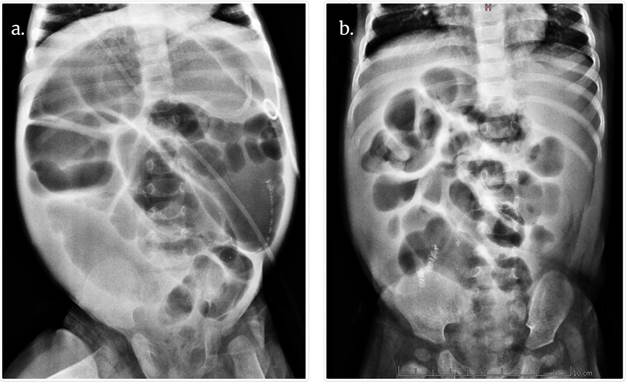

En la (Fig.2) se observa la comparación entre radiografías simples de abdomen del pre y postoperatorio, nótese la diferencia en el calibre de las asas.

Fig.2 Radiografías simples de abdomen. a) Radiografía preoperatoria de procedimiento de Bianchi, gran dilatación de asas yeyunales; colon de menor calibre sin su posición anatómica normal dado su condición previa de malrotación por su gastrosquisis. b) Postoperatorio de Bianchi, nótese la disminución franca de diámetro de asas luego de la cirugía. Fuente: autores